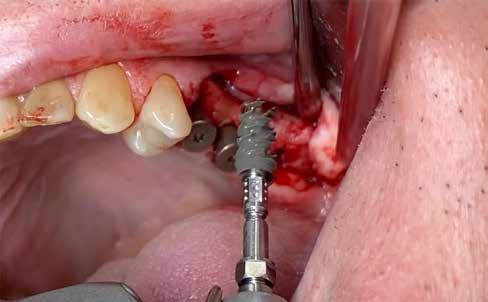

A sebészi fázis

Helyi érzéstelenítésben a 2.5-ös fog mentén intraszulkuláris metszést végeztünk, hogy minimalizáljuk a lágyszövetet érő traumát az extrakció során. Ezt követően kresztális metszést végeztünk a 2.5-ös fog disztális részétől egészen a tuber végéig, és a teljes vastagságú lebenyt preparáltuk, hogy feltárjuk az állcsontgerincet.

A 2.5-ös fog mentén periotómot haszáltunk, hogy átvágjuk a periodontális rostokat, így a fogat kilazítottuk, hogy ezzel is csökkenthessük a fogó által végzendő laterális mozgások szükségességét, illetve hogy a környező csontot is a legnagyobb mértékben megőrizzük. Nem volt elég csont (anélkül, hogy perforálnánk az arcüreg alapját) ahhoz, hogy abban stabilizáljuk az implantátumot, úgy döntöttünk, hogy behelyezünk egy ∅ 5.0 x 12 mm-es Straumann® BLX implantátumot közvetlenül az alveolusba, előfúrás nélkül. Az implantátum menetkialakítása lehetővé tette, hogy a kézidarabbal behajtva, 25 Ncm-es nyomatékot érjünk el, majd racsnis nyomatékkulcs segítségével juttattuk a végső pozíciójába, 80 Ncm-es behajtási nyomatékot mérve (3. és 4. ábrák).

A 2.6-os fog helyén egy 6 mm mély furatot készítettünk a gyártó előírása szerint, a puha csont protokoll lépéseit követve. Egy ∅ 5.0 mm × 6 mm Straumann® BLX implantátumot helyeztünk be 50 Ncm-es behajtási nyomatékkal (5. ábra)

A 2.7-es fog helyénél egy disztális irányú, 14 mm mély, ferde előfúrást végeztünk, elkerülve a sinus maxillarist a tuber csontkínálatának felhasználásával. Egy ∅ 5.0 mm x 14 mm Straumann® BLX implantátumot helyeztünk be, 50 Ncm-es behajtási nyomatékkal (6. ábra)

Mind a három implantátumba gyógyulási csavar került, ezzel elkerültük az újabb sebészi beavatkozás szükségességét.

Tovafutó varrattal zártuk a sebet az ínyformázó csavarok körül (7. és 8. ábrák).

3. ábra: Straumann® BLX implantátum ∅ 5.0 mm x 12 mm – készen a behelyezésre a 2.5-ös fog helyére. 4. ábra: A végső behelyezési nyomaték 80 Ncm volt a nyomatékkulcs alapján. 5. ábra: Straumann® BLX implantátum ∅ 5.0 mm x 6 mm – készen a behelyezésre a 2.6-os fog helyére. 6. ábra: Straumann® BLX implantátum ∅ 5.0 mm x 14 mm – készen a behelyezésre a 2.7-es fog helyére.